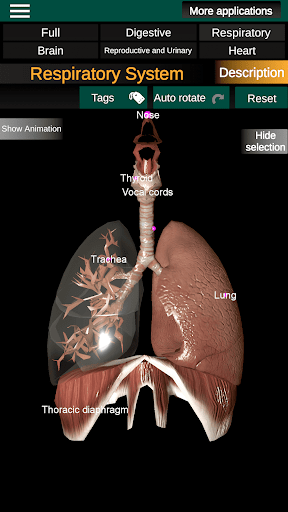

* Дихальна система, яка включає трахею, бронхи, легені та анімацію цієї системи.

* Легкий доступ і навігація (масштабування, 3D-обертання).

* Описи кожного органу.